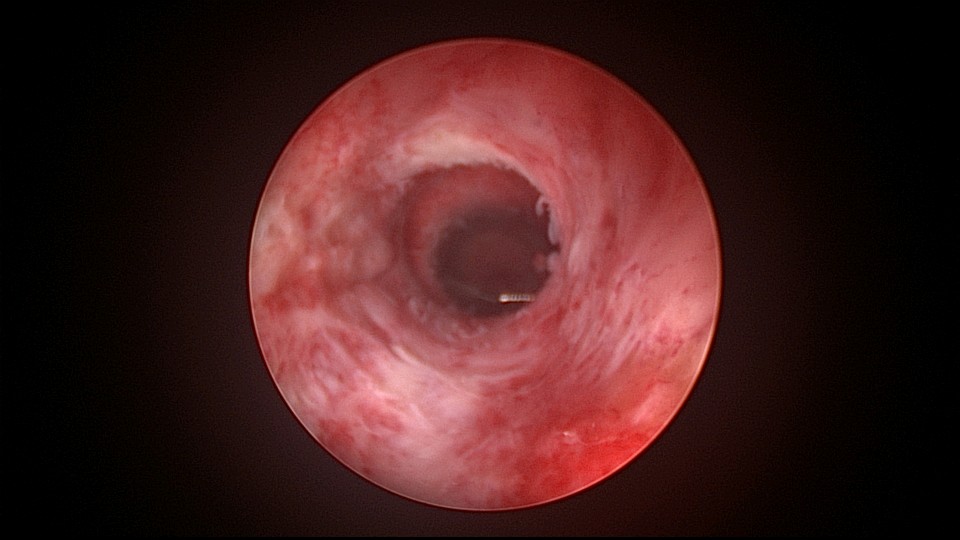

患者38岁,G5P1,剖宫产1次。2023年1月节育环下移带环受孕,宫腔镜取环终止妊娠,同时行左手上臂内侧皮埋避孕,遗憾的是手术医生术中没有找到节育环,术毕复查B超,环仍在宫腔,第二天宫腔镜探查,节育环位于切口憩室内,取出节育环。再次遗憾的是取环后阴道淋漓不净出血,术后第24天复查B超见胚物残留,第三次宫腔镜手术清除残留组织。2025年10月取出皮埋棒,2025年11月外院安环,术后2周复查B超环下移,2025年12月(月经干净3天后),安环医院取出节育环,取环后第6天到我院行宫腔镜安环并做节育环固定。子宫水平位,宫深8.5cm,见切口憩室比宫腔更宽大,形成类似金字塔形状(2次节育环下移原因),行宫腔镜下缝合线结固定节育环,打了3个结,拉过缝合点2个结。第十七例节育环固定。既往带环受孕,多次宫腔镜手术。术后2周复查B超,节育环位置正常,环顶端距宫底1.6cm。